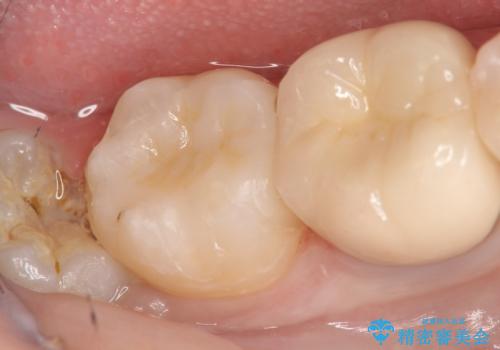

- 右下7の銀歯を白くしたいといらっしゃった方の症例です。

銀歯及び虫歯を除去後、セラミックインレーで修復を行いました。

当院のセラミックインレーはemaxという強度と審美性に優れた材料を使用しています。

またプレス方式でインレーを製作しているため、削り出しで製作するCADCAMより優れた適合性も持ち合わせており、虫歯が再発しにくい修復物です。